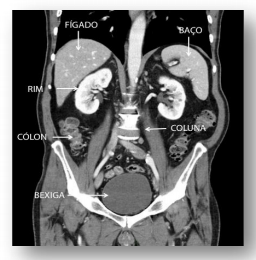

“Por seu papel contundente na detecção de diagnósticos clínicos, é necessário um profissional treinado para realizar a Tomografia Computadorizada, conhecimentos de Anatomia, Fisiologia, Radiologia, Física, entre outros, são cruciais para a formação do profissional e, posteriormente, para garantir uma imagem com qualidade para a abordagem clínica correta com o paciente” (MACIEL E JÚNIOR, 2015).

Observando a imagem acima e usando os conhecimentos sugeridos no trecho escrito escolha a opção que traz apenas as proposições verdadeiras.

I - A retirada do cólon, esplenectomia, pode ser importante em quadros complicados de digestão.

II - Ao contribuir diretamente com a hematose e enurese, o fígado executa outras inúmeras funções.

III - O rim promove o controle do equilíbrio hidroeletrolítico sendo a sede da filtração glomerular.

IV - O baço é o órgão que se lesiona com mais frequência no abdômen quando há pancadas violentas no lado esquerdo.

Marque as opções verdadeiras: